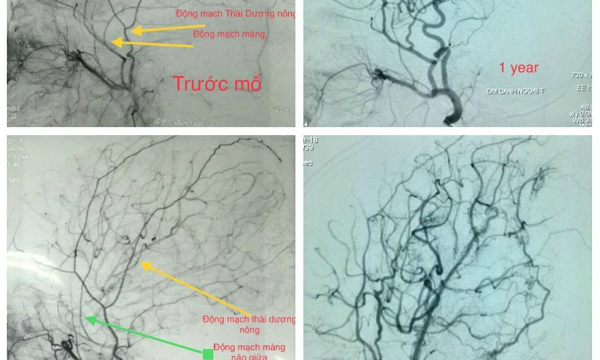

Kiểm tra hình ảnh của bệnh nhân Moyamoya trước và sau khi phẫu thuật.

Trong những năm gần đây, bệnh viện nhi đã điều trị cho khoảng 30 bệnh nhi Moyamoya với 2 điều. Đứa trẻ được đánh giá, kiểm tra các mạch máu trong não và sau đó sẽ tiến hành phẫu thuật để cung cấp nguồn máu mới cho não. Theo dõi cho thấy, sau ca mổ, nhiều trẻ không còn bị thiếu máu não tái phát, được kiểm tra lại mạch máu não quan sát thấy sự kết nối tốt giữa bên ngoài và não để cung cấp máu lên não. Một số trường hợp do điều trị muộn, tổn thương do tai biến mạch máu não trước đó quá nặng nên sau khi mổ vẫn còn các vệt thần kinh.